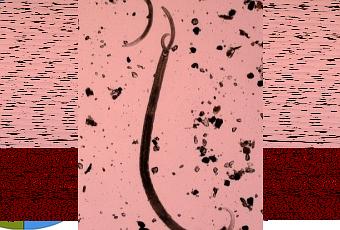

C'est en travaillant sur des vers nématodes que l'équipe de chercheurs réunie autour du Dr Bastiani a réalisé ces découvertes, expliquées dans la revue Science.